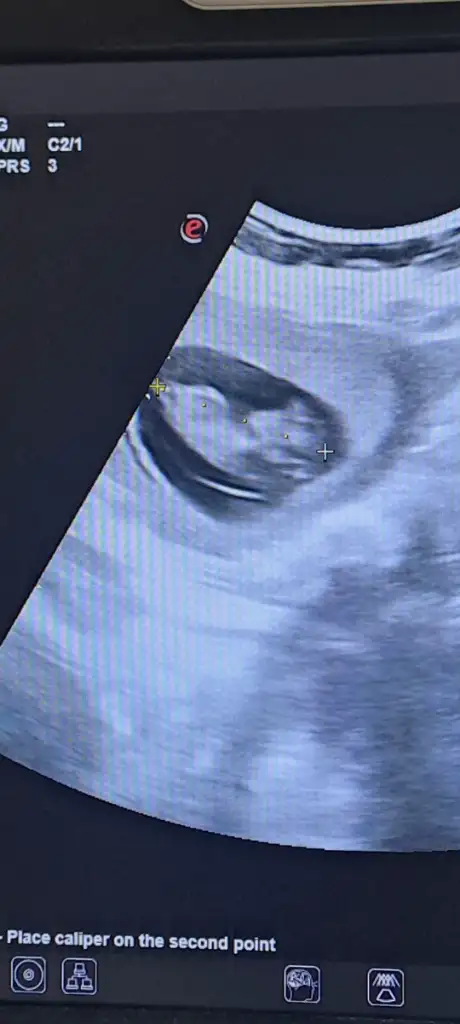

Merhaba, benim bebeğimde 10+4 bir tahmin yapılabiliyor mu acaba 🥰